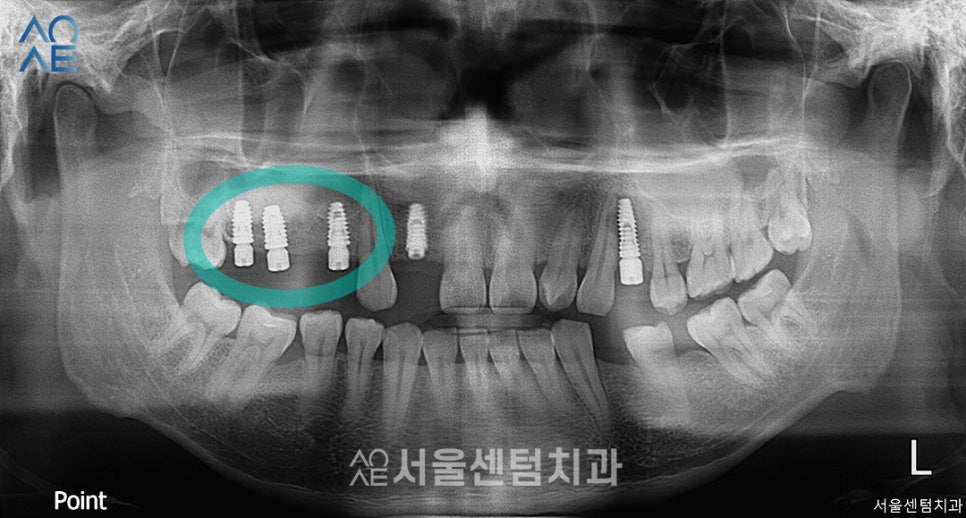

또 2주 뒤 세번째 수술을 진행합니다.

이번엔 아래-오른쪽 어금니입니다.

- 05

아래-왼쪽 실밥 제거 후

한 달 뒤 임플란트의 상태를 확인해봤습니다.

잇몸뼈는 잘 형성되어갔고

식립한 부분도 안정적으로 자리를 잡았습니다.

이 날은 수술한 부위 체크도 해드리고

사랑니에 대해서도 상담을 해드렸습니다.

사진에 표시한 윗쪽 두개입니다.

사랑니 발치 후 3주 뒤에

제일 처음 식립했던 임플란트 2차 수술도

진행하기로 했습니다.

다른 부위는 일체형으로 식립하여 괜찮지만

앞니쪽은 픽스처만 식립하여

2차 수술이 필요했기 때문이죠.